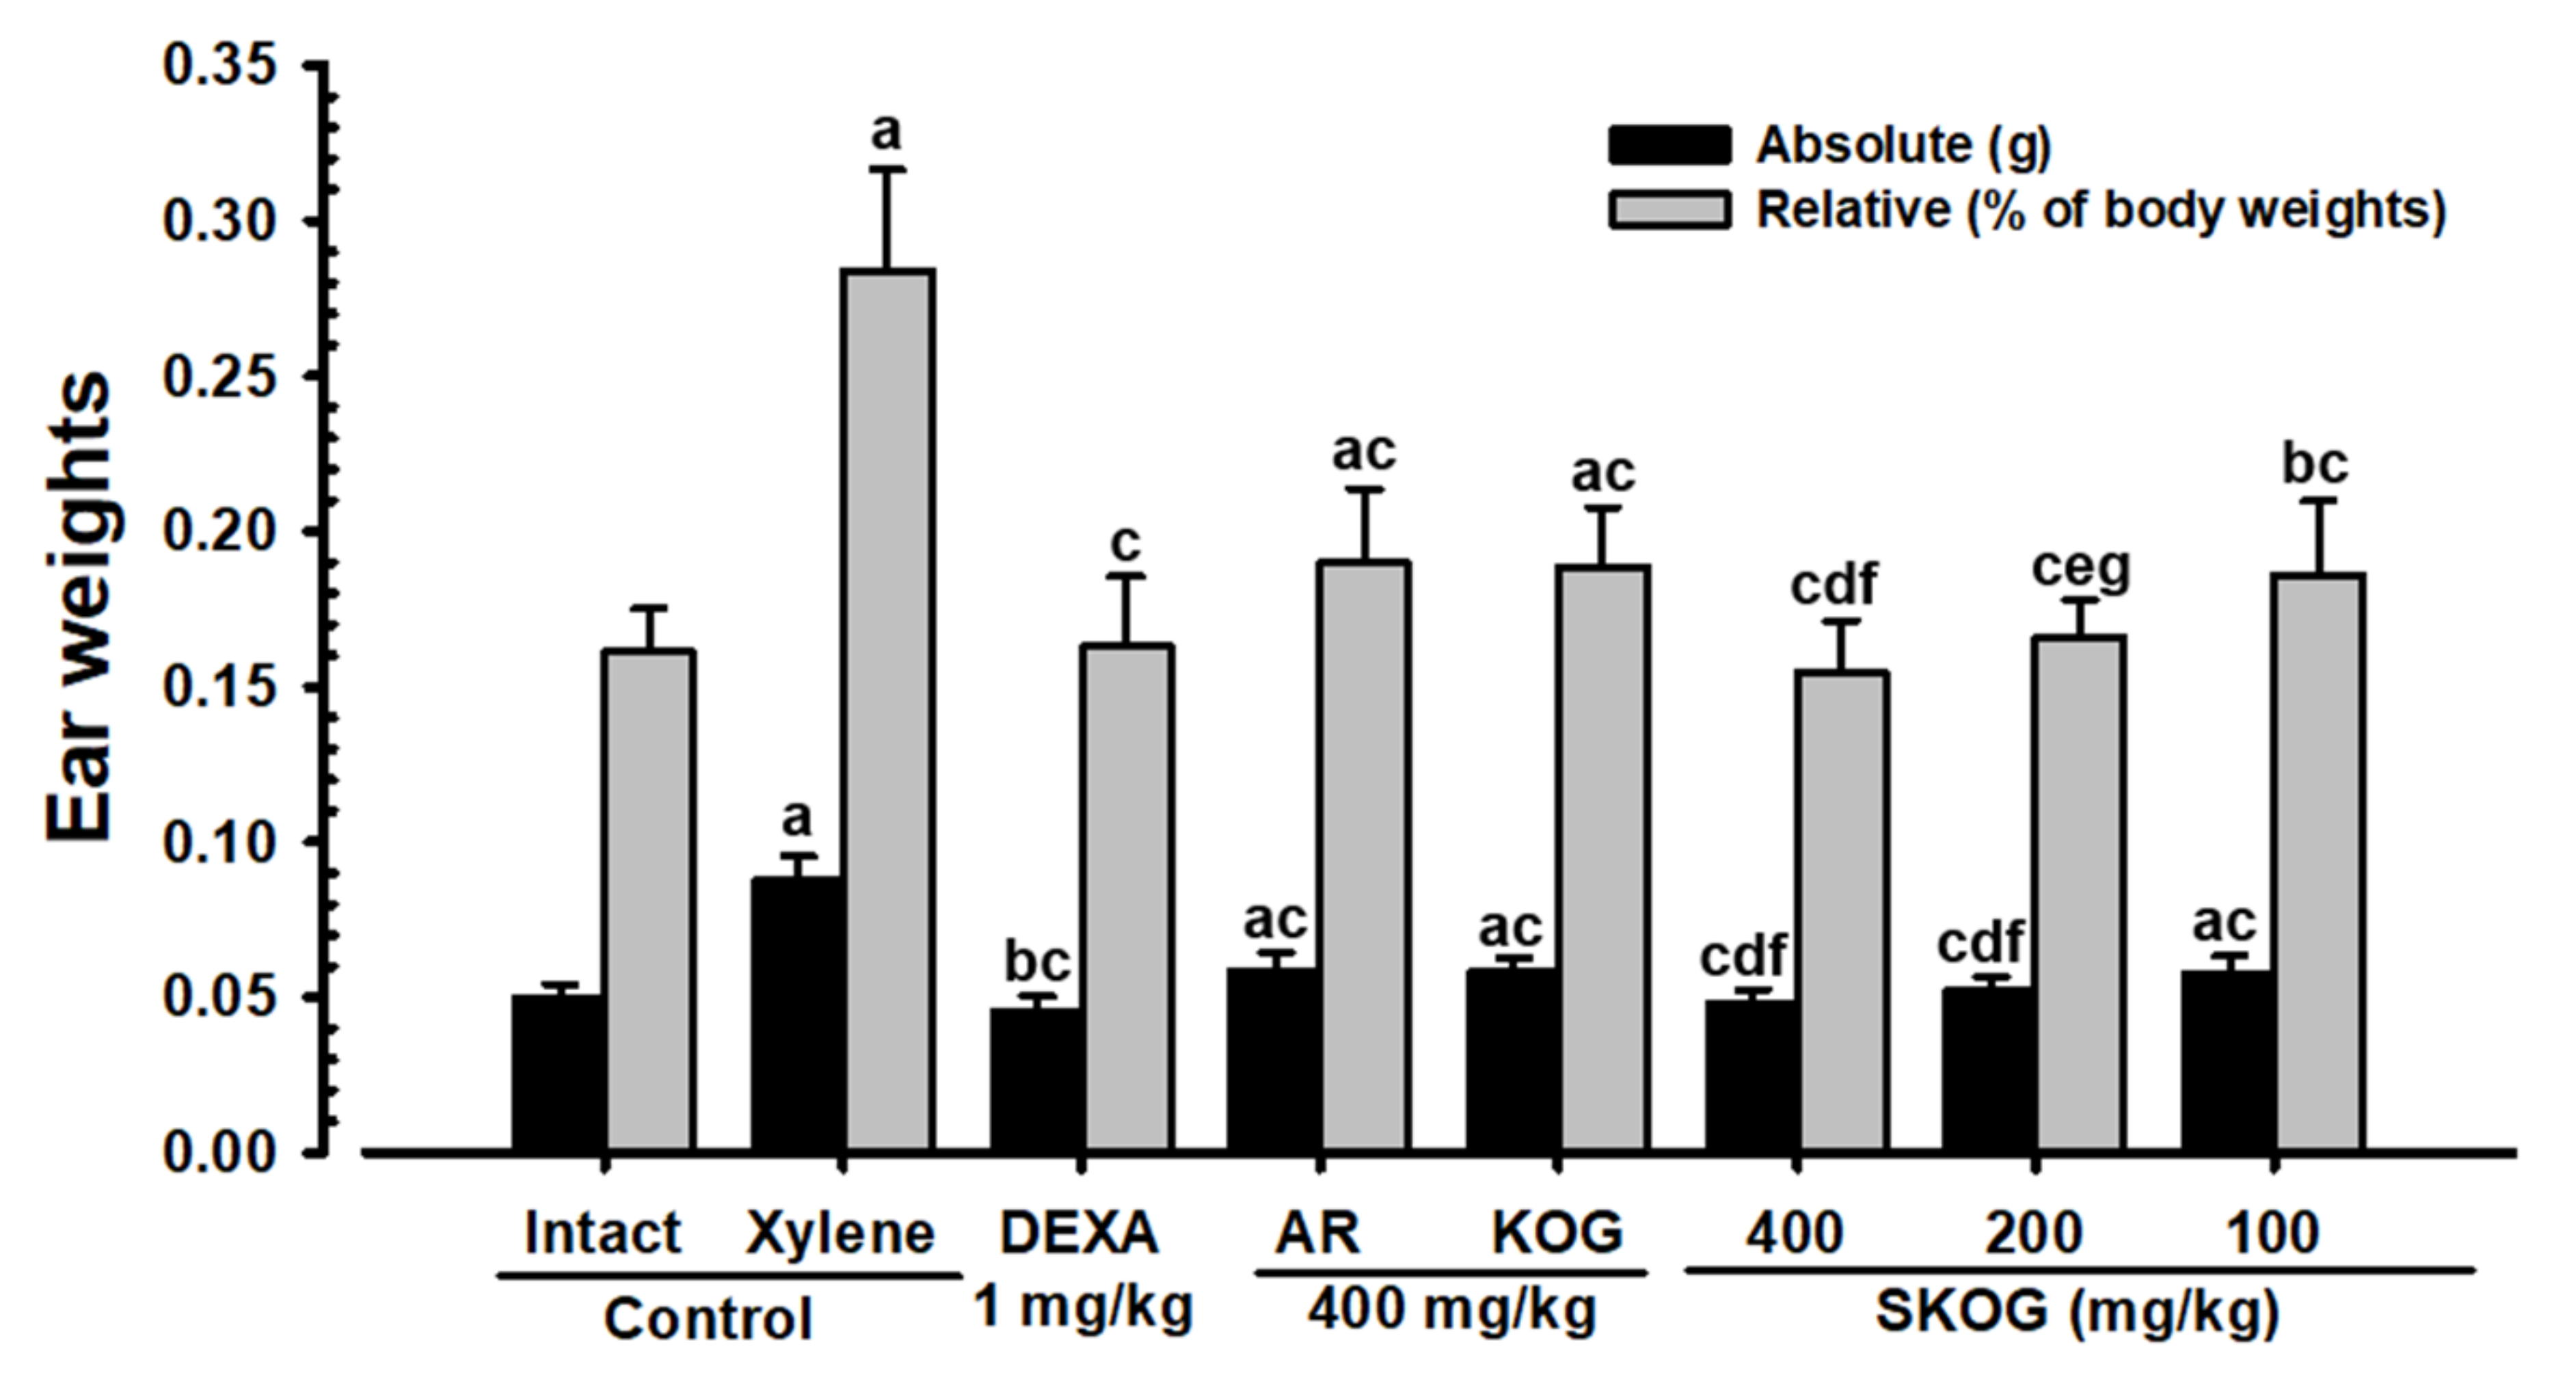

3.4.3. Changes in Ear Weight

3.4.4. Histopathological Findings on the Ear